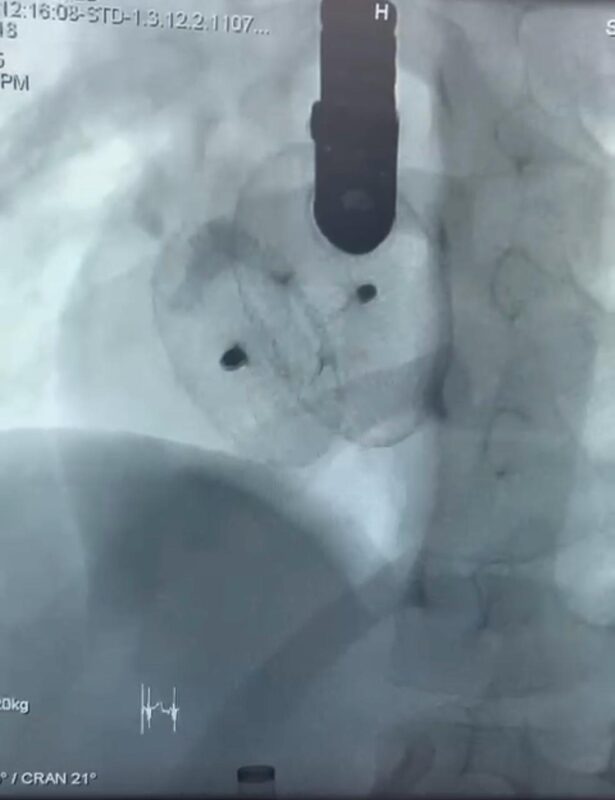

وقال الدكتور مجدي القاضي عميد كليه الطب البشري ورئيس مجلس اداره المستشفيات الجامعيه ، بان العمليات الثلاث تمثل نقله نوعيه في علاج العيوب الخلقيه بالقلب لدى الاطفال ،حيث تمت باستخدام القسطره التداخليه دون الحاجه الى تدخل جراحي مفتوح ، مما يسهم في تقليل معدلات المضاعفات وتسريع معدلات الشفاء.

واوضح الدكتور احمد كمال عبد الحميد المدير التنفيذي للمستشفيات الجامعيه انه تم علاج الطفله حور ثلاث سنوات والتى كانت تعاني من ثقب بين الاذنين ، وتم غلقه باستخدام جهاز امبلاتزر ، والطفله مريم علي ست سنوات والتي كانت تعاني من ثقب بين الاذنين مصحوب بتضخم في القلب ونقص في النمو ، وتم علاجها باستخدام جهاز لايف تك ، والطفله فاطمه 13 سنه والتى كانت تعاني من ثقب بين البطينين ، وتم اغلاقه باستخدام جهاز كونار لايف تك ، وهو من احدث اجهزه اغلاق الثقوب عالميا .